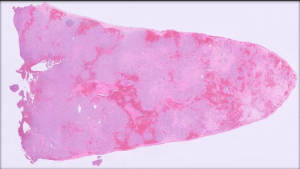

Figure 2: Low power view of the spleen showing near diffuse effacement of normal architecture by a proliferation of neoplastic epithelial cells.